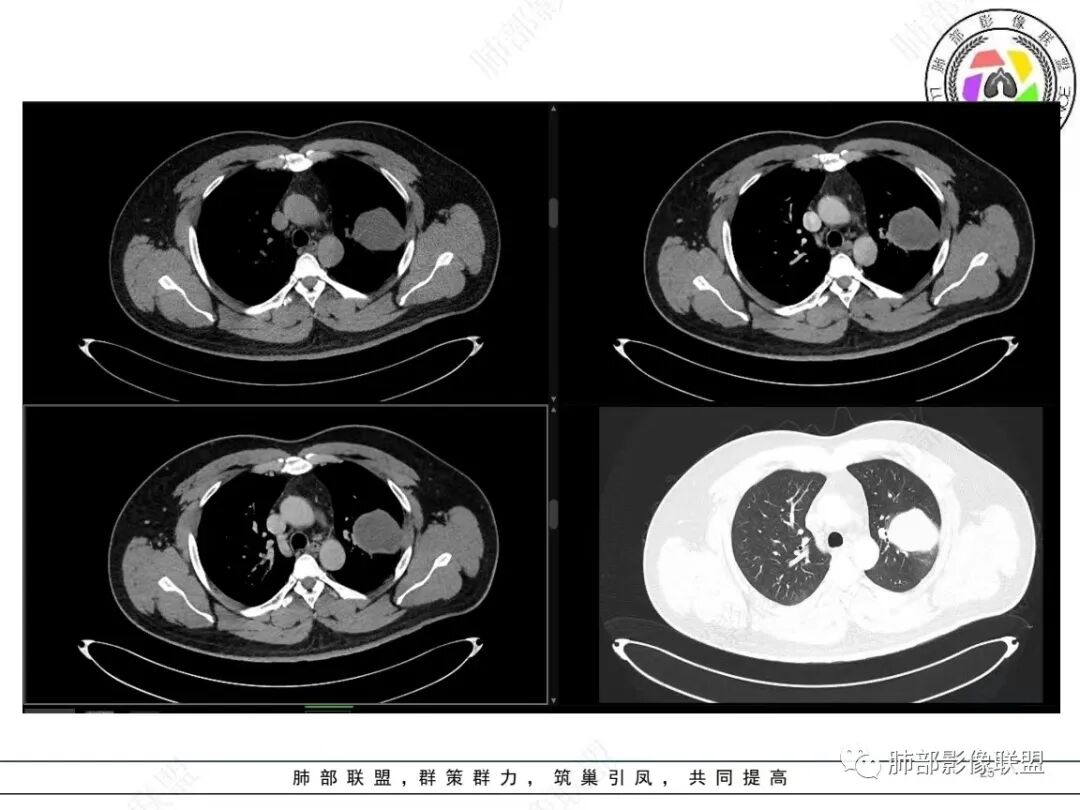

中年人,咳血,左肺上叶实性团块,边界清晰,与胸膜分界不清,可见栽赃表现,病灶推挤支气管及肺血管内移,增强可能条纹血管影,总体强化明显,考虑恶性或交界性肿瘤,间叶组织来源,肉瘤,SFT,肉瘤样癌,滑膜肉瘤。

左肺上叶胸膜肿块,浅分叶,边缘光整,密度不均匀,周围气管及血管受压推移,边缘强化,考虑肉瘤,鉴别SFT

左肺上叶占位,平扫密度较低,临近胸膜栽赃桩,外向内生长,边缘有膨隆、毛糙,增强后轻度强化,边缘弧线样强化,考虑肉瘤样癌

左上肺软组织肿块,周围散在磨玻璃影,界不清,窄基底贴于胸壁,胸膜下脂肪间隙不清,呈低强化,胸膜下见。与主病灶强化方式一样的病变,2R区见肿大淋巴。考虑恶性,间叶组织来源合并出血。

青年男性,咯血;CT示左肺上叶胸膜下软组织肿块,边界尚清,宽基底与胸膜相连,增强动脉期内见细条状血管影,轻度延迟强化,定位:肺外,胸膜外脂肪存在,考虑脏层胸膜起源;定性:考虑SFT。

影像表现:左肺上叶占位合并出血,胸膜栽赃,边缘强化,局部见血管影,中心密度20Hu,无强化,符合非液化坏死。定位:肺内,定性恶性(明显血管影,栽赃排除错构瘤,中心无强化排除PSP,无明显清楚的坏死边界,强化不符合肉芽肿,排除结核),年龄轻,无长时间吸烟史和肺气肿改变,肉瘤样癌可能性很小,与支气管无确切关系,所以病理类型考虑来源于肺间叶组织的肉瘤,骨外尤文?滑膜肉瘤?

有血供,强化不明显,周围肺出血,肺组织受压改变,定位肺外,胸膜增厚,部分胸膜下脂肪间隙存在,不确定肋骨是否受侵犯,部分层面与肺动脉分界不清,感觉推移,如果供血要考虑sft,强化不符合,有血管进入,但是强化不明显,密度相对均匀,所以不考虑坏死,富含粘液可能,咯血,说明累及支气管了,有一定侵袭性,肿块大,考虑间叶来源肿瘤,与胸膜接触面相对不是宽基底,综合考虑滑膜肉瘤可能,典型的滑膜肉瘤一般铺路石改变,这个又觉得信号相对均匀了一些学习中

定位肺内明确,来源间叶组织明确,年龄和吸烟史情况排除肉瘤样癌,剩下的就基本上只有骨外尤文和滑膜肉瘤了,再加上强化低,骨外尤文就肯定首先考虑。